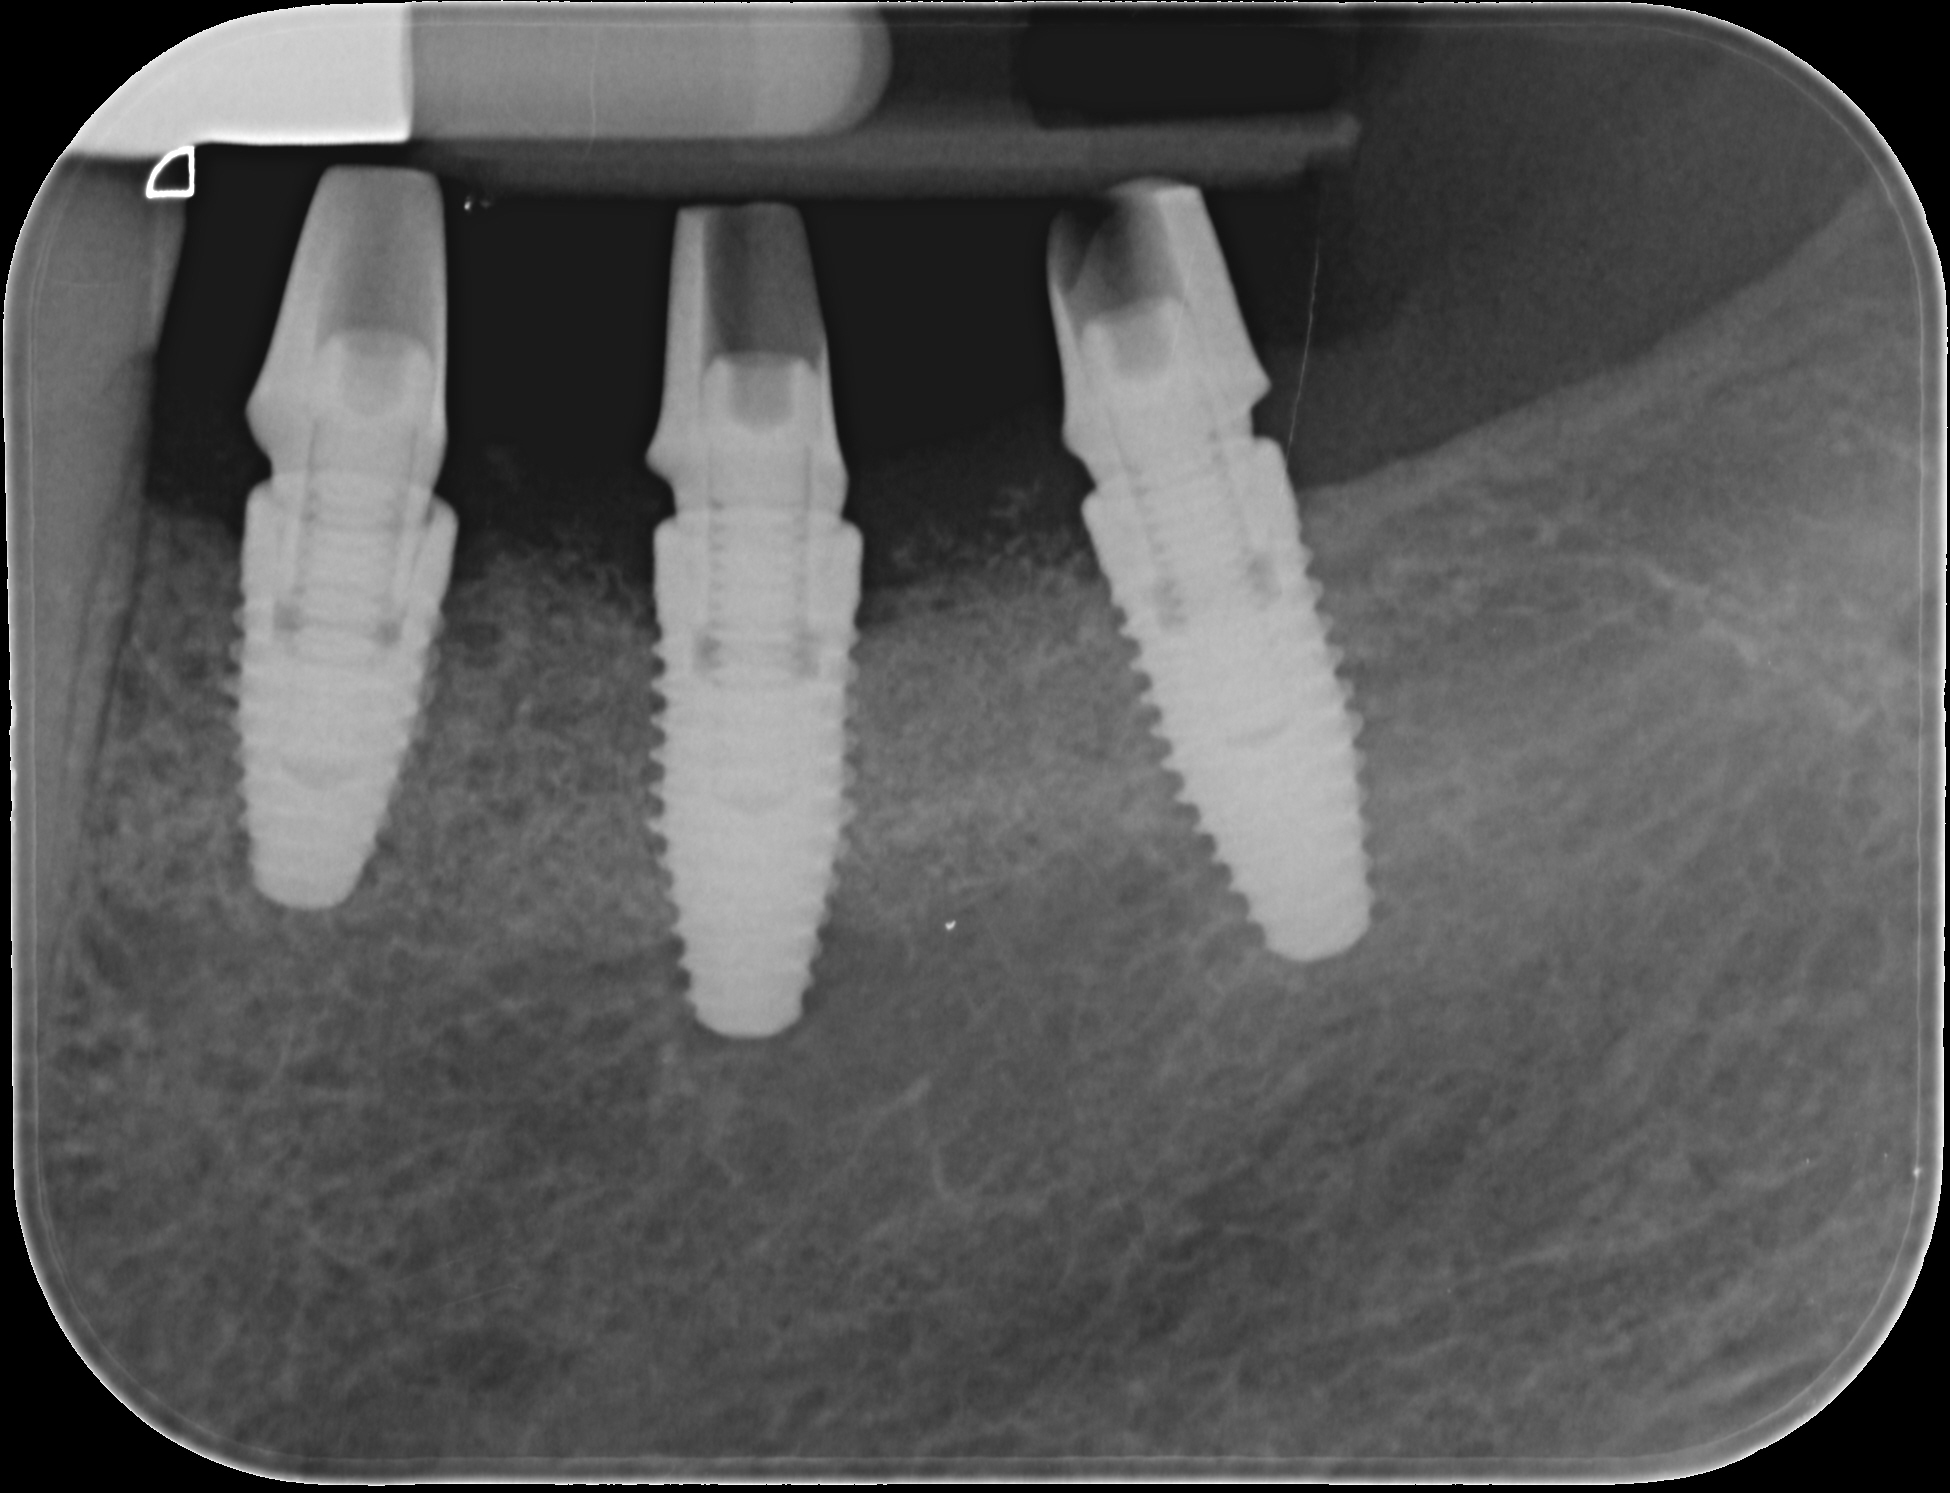

Replacement of a fixed partial denture with three implants

A 52-year-old patient is a referral and has been wearing an immediate provisional partial denture after replacement of her worn and fractured fixed partial denture. As a definitive treatment solution, the patient desired "beautiful and long-lasting" implant-supported single crowns. Clinically the CT-scan revealed a very narrow bone crest ("knife-edge") in the 3rd quadrant. Implant placement has been planned with a simultaneous GBR procedure.